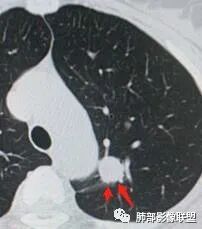

一、先讨论GGN吧

1、密度?MGGN?PGGN?

2、边界?清?不清?

3、有无收缩力?有胸膜牵拉?毛刺?

4、血管连通 移动:3型?4型?

两条都进入,相互交通-4

常规判断还需要大小、CT值

大家诊断啥?

wj9527

IAC>MIA

金豆

MIA

lmg

微浸润腺癌

南边

为啥不是原位?

蔡磊

有收缩,牵拉

血管进入增粗,胸膜牵拉

有月牙 两条都进入,相互交通-4 胸膜牵拉

二.左肺上叶前段磨玻璃结节:

该结节较大,边界清楚,小叶间隔阻挡特征相当明显,微浸润腺癌的诊断几乎没有争议!